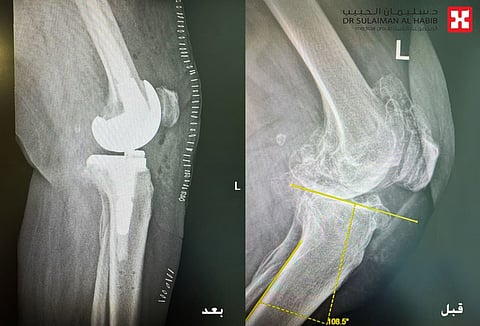

وقال الدكتور سكيك عند وصول المراجعة للعيادة تم الإستماع إلى شكواها والإطلاع على ملفها الطبي، وتبين أنها تعاني من آلام حادة وانتفاخ شديد بالركبة اليسرى منذ سنوات، وعدم القدرة على المشي أو صعود السلم، على الفور تم إخضاعها لفحوصات طبية دقيقة بالأشعة السينية (Digital X-rays) على كافة إتجاهات الركبة، بالإضافة إلى التحاليل المخبرية، مشيراً إلى أن النتائج كشفت عن وجود خشونة شديدة وإحتكاك من الدرجة الرابعة، وتآكل بالغضاريف المحيطة بالركبة اليسرى، وكذلك الكشف عن تكلسات خلف الركبة، بالإضافة إلى حدوث إنحراف وتقوس بالركبة، وكذلك إصابتها بمجموعة من الأمراض المزمنة مثل ضغط الدم والكوليسترول وهشاشة عالية بالعظام.

موضحاً بأنه بعد الإنتهاء من دراسة كافة نتائج الفحوصات، تم إتخاذ القرار بالتدخل الجراحي، مشيراً إلى أن العملية استغرقت ساعتين ونصف تحت التخدير الجزئي، وتم فيها استخدام تقنية الروبوت الجراحي المتطور، والذي تم تزويده بالمعلومات الخاصة بالمراجعة، حيث يقوم الروبوت برفع قياسات مفصل الركبة بشكل دقيق، وتحديد المفصل الصناعي المناسب، مما يمنح الحالة نتائج عالية الدقة، وبما يتناسب مع بنية الركبة والأنسجة المحيطة بها، كما تم تعديل إنحراف وتقوس الركبة من خلال استخدام دعامة متطورة بالساق والفخذ.